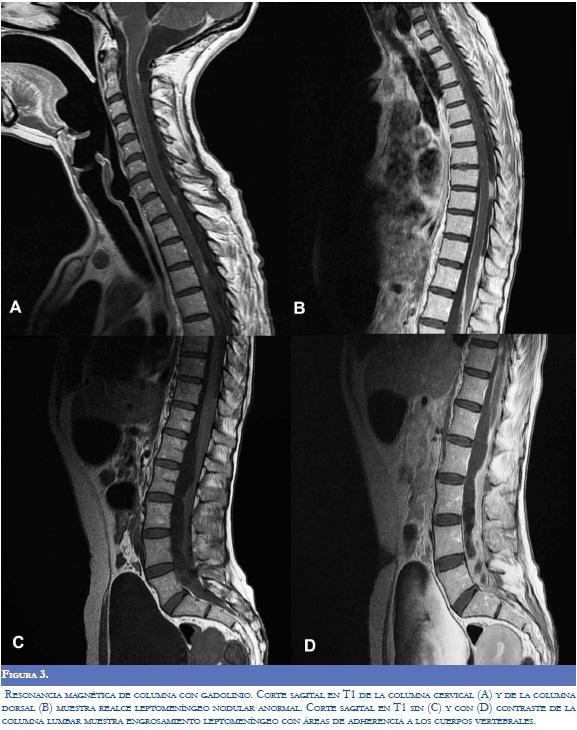

Los laboratorios realizados (hemograma, electrólitos, proteína C-reactiva, VDRL y VIH) fueron normales. Se realizó punción lumbar pero no se obtuvo retorno de líquido cefalorraquídeo (LCR) por bloqueo del espacio subaracnoideo. El LCR se obtuvo por medio de ventriculostomía externa y su análisis mostró hipoproteinorraquia; posteriormente se realizó derivación ventriculoperitoneal y se realizó un segundo análisis de LCR (Tabla 1). La reacción en cadena de polimerasa para tuberculosis fue negativa en LCR (otros análisis se encontraron normales). Los niveles de inmunoglobulina G en sangre fueron positivos para cisticerco (Índice IgG de 4,57; V.R. menor de 0,35). La primera resonancia magnética del cerebro realizada al ingreso al servicio de urgencias mostró marcada hidrocefalia (Figura 1). Después de la ventriculostomía externa, y la colocación de la derivación ventrículoperitoneal, la tomografía axial computarizada del cerebro (TAC) mostró múltiples nódulos calcificados sugestivos de NCC sin edema perilesional (Figura 2). La RM de la médula espinal reveló paquimeningitis generalizada, realce meníngeo y lesiones nodulares sugestivas de NC subaracnoidea (Figura 3). Otros estudios imaginológicos como TAC toracoabdominal con contraste y gamagrafía ósea se encontraron dentro de los límites normales. La biopsia meníngea realizada reveló la presencia de células fibrosas monomórficas rodeadas por tejido colagenosos, sin parásitos, compatible con inflamación crónica o hidrocefalia crónica.

Otras localizaciones de la NCC incluyen el espacio intraventricular en el 33% de los casos, el cuarto ventrículo es el más afectado, seguido por los ventrículos laterales, tercer ventrículo y por último el acueducto (7). La cisticercosis ventricular se observa en la TAC como lesiones hipodensas que distorsionan el sistema ventricular causando hidrocefalia obstructiva o asimétrica (10). La forma subaracnoidea corresponde al 2-12% de los casos y las imágenes muestran un compromiso difuso con aracnoiditis, hidrocefalia, vasculitis con o sin compromiso isquémico (1). La cisticercosis medular puede ocurrir con menor frecuencia y puede estar asociada con mielopatía debido a la invasión intramedular del quiste (2); los hallazgos radiológicos se resumen en la tabla 2.

El compromiso neurológico se produce por las formas activas e inactivas de la NCC. Las manifestaciones clínicas y los hallazgos imagenológicos dependen de la localización de las lesiones en el SNC, la respuesta inflamatoria, el compromiso en la circulación del LCR y la etapa de la enfermedad. Este caso tuvo una gran variedad de manifestaciones neurológicas estrechamente relacionadas con el compromiso difuso del SNC. En la evaluación clínica y neuroimagenológica se demostró una NCC nodular calcificada con hidrocefalia, compromiso medular y trastornos motores. La TAC y la RMN mostraron una forma meníngea crónica de la NC con compromiso espinal caracterizado por la presencia de hipertensión intracraneal secundaria a aracnoiditis generalizada y adherencias que ocasionaron obstrucción del flujo del LCR e hidrocefalia. Hubo aracnoiditis cerebral y espinal. La paciente tuvo convulsiones recurrentes y síntomas motores explicados por nódulos focales e hidrocefalia, hipertensión intracraneal y aracnoiditis medular, respectivamente.